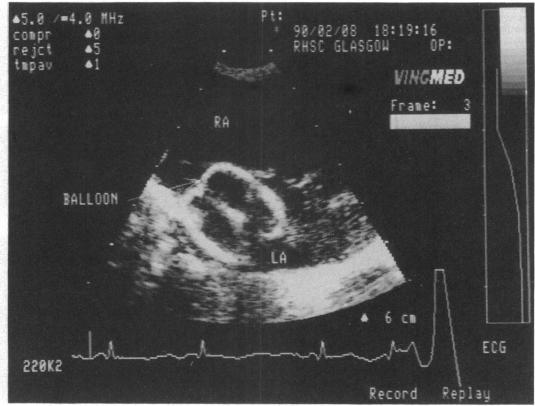

超声心动图引导下的球囊房间隔造口术:六年经验及经脐静脉插管实用性评估

Balloon atrial septostomy was undertaken under cross sectional echocardiographic control in 63 consecutive infants: in no case was fluoroscopic imaging required. The procedure was performed in the cardiac catheterisation laboratory, ward side room, or at the bedside in the neonatal intensive care unit. Catheterisation via the umbilical vein was attempted in 37 infants aged less than 48 hours old and was successful in 27. No complication was clearly attributable to the procedure though two infants died. A nine day old child died from disseminated intravascular coagulation the day after septostomy by the iliofemoral route and another, aged nine days, died of necrotising enterocolitis which had developed when he was eight days old, after umbilical catheterisation at eight hours. Balloon atrial septostomy is a safe and easy procedure under cross sectional echocardiographic imaging control. Catheterisation via the umbilical vein was safe, easy to perform, and is appropriate in infants aged less than 48 hours.

在连续63例婴儿中,在横断面超声心动图引导下进行了球囊房间隔造口术:无一例需要荧光透视成像。该操作在心脏导管实验室、病房侧室或新生儿重症监护病房床边进行。对37例年龄小于48小时的婴儿尝试经脐静脉插管,27例成功。尽管有两名婴儿死亡,但无明确的并发症可归因于该操作。一名9天大的儿童在经髂股途径进行房间隔造口术后第二天死于弥散性血管内凝血,另一名9天大的儿童在8小时大时经脐静脉插管后,8天大时发生坏死性小肠结肠炎并死亡。在横断面超声心动图成像引导下,球囊房间隔造口术是一种安全、简便的操作。经脐静脉插管安全、易于操作,适用于年龄小于48小时的婴儿。